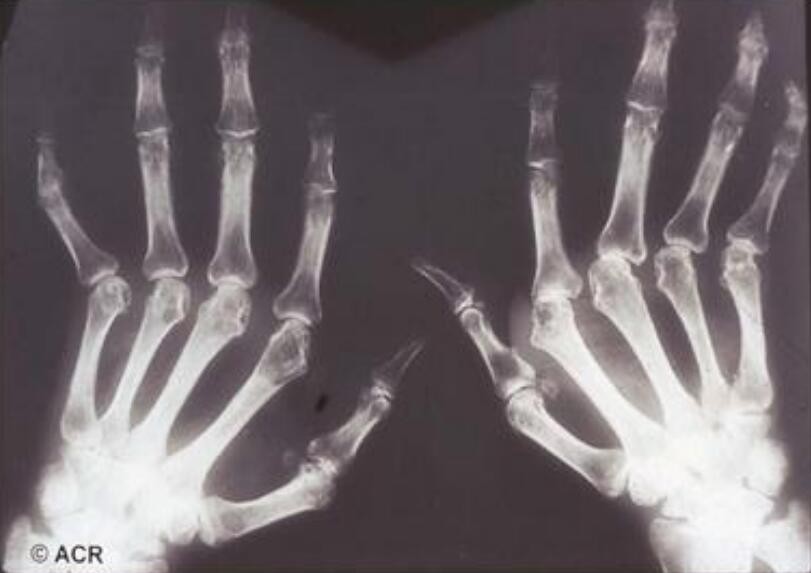

风湿吃蜂王浆还是有一定好处的,风湿大多有关节病变和症状,会有红肿、疼痛以及功能受损等多方面炎症的表现。蜂王浆中的王浆酸有很强的杀菌消炎的作用,可以清除身体内的一些细菌,对于炎症和红肿都有一定的缓解作用。